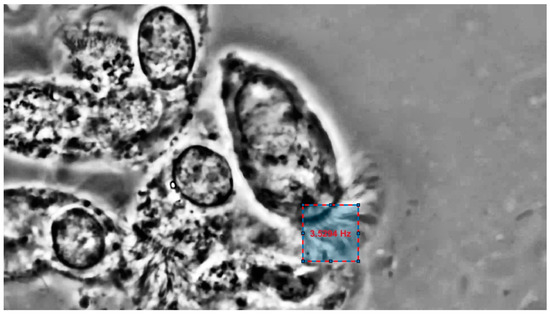

| Cilia 4 | 3.500 | 3.529 | 0.029 |